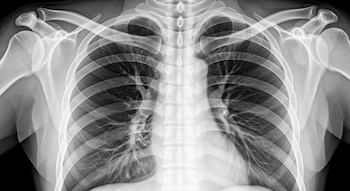

Cómo se estudió el microbioma pulmonar

Para llevar adelante el análisis, los científicos trabajaron con 100 personas sanas y 163 pacientes con distintas afecciones respiratorias. Las muestras se obtuvieron mediante broncoscopía estéril, un procedimiento que permite recolectar material directamente de las vías respiratorias profundas.

Este detalle es importante porque reduce la posibilidad de contaminación con microorganismos de la boca o la garganta, lo que mejora la precisión de los resultados.

A diferencia de investigaciones previas, que analizaban muestras de esputo —más propensas a contaminación—, este trabajo se centró en material obtenido de zonas profundas del pulmón.